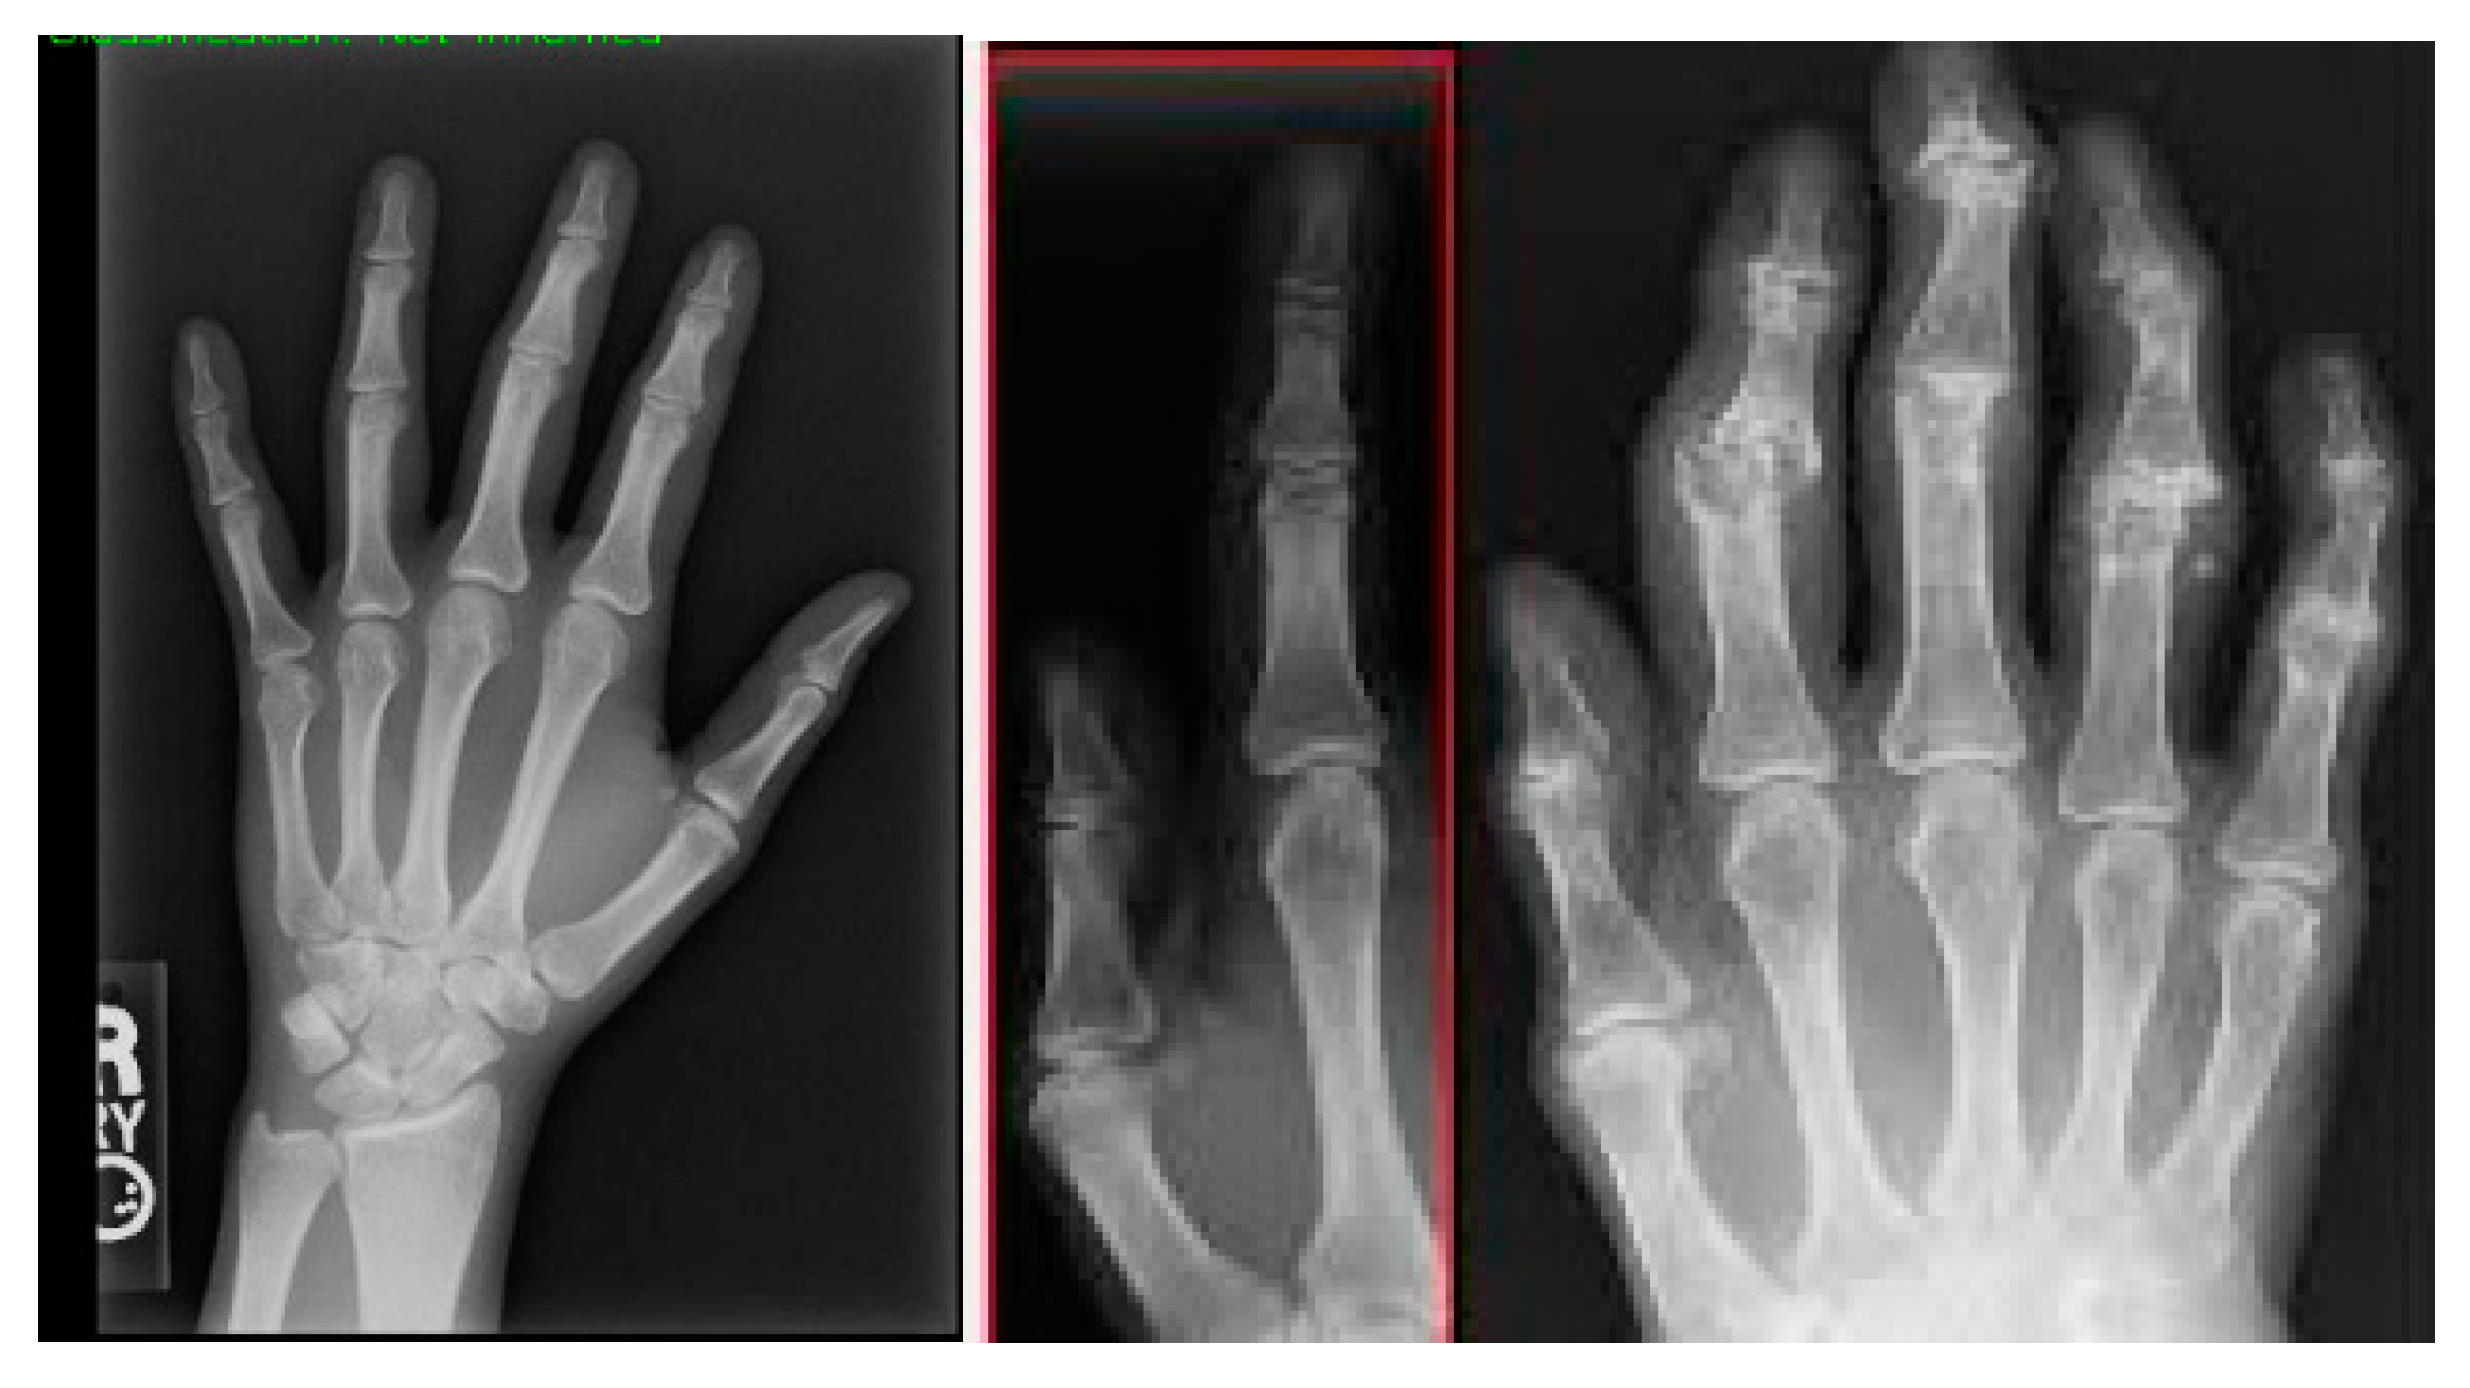

Figure 2 covers the visualization of the mini set of images after transforming it via data augmentation. Image transformations including rotation, scaling, flipping, and brightness modifications have been added to these images to make the training dataset more lively and informative. The artificial images with variety boosted the machine learning models and led to better robustness and generalization ability of these models in case the real-world data varied a lot.

Figure 2. A sample of images after data augmentation.